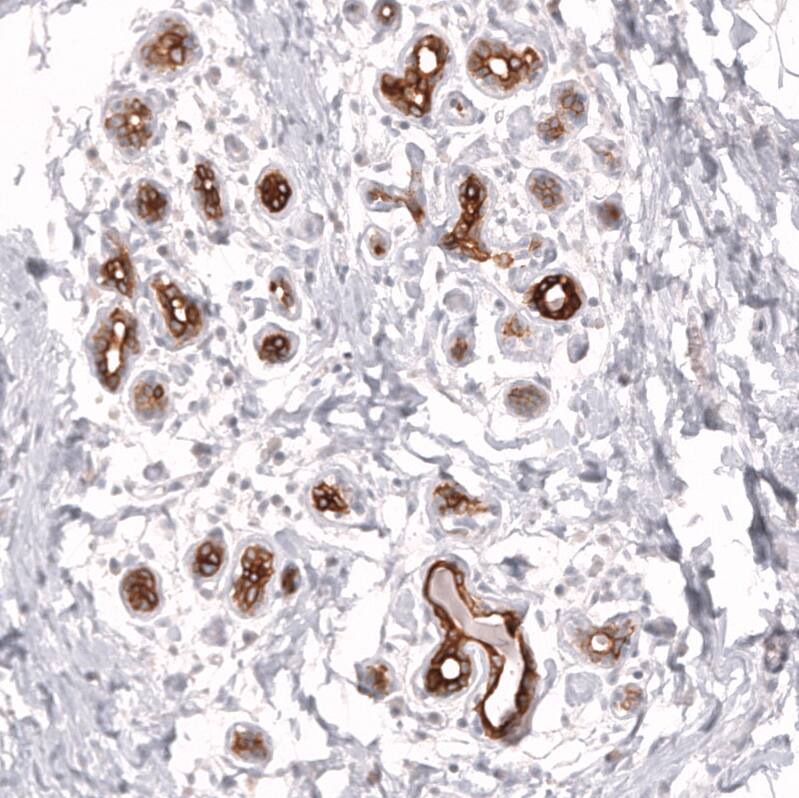

Staining of human epididymis shows strong membranous positivity in glandular cells.